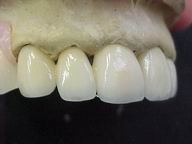

Reabilitação funcional e estética em ambas as arcadas

com próteses fixas e removíveis de encaixe de precisão.

DEPOIS

Fase Intermediária Vista Frontal